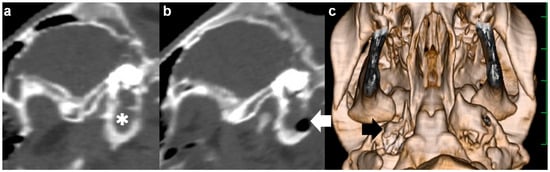

The animal was positioned in dorsal recumbency with the neck extended via a cushion beneath it. A 15 cm incision was made longitudinally in the right paramedian cervical skin caudally to the medial level of the angle of the mandible (Figure 3a). Through blunt dissection of the subcutaneous tissues, the sternothyroid and omohyoid muscles were identified as running in parallel and along the longitudinal incision (Figure 3b). Blunt separation between the sternothyroid and omohyoid muscles confirmed the right external carotid artery running along the trachea palpated at the medial aspect of the incision, allowing the observation of the right vagus nerve running in parallel with it. Two Gelpi retractors were used in the cranial and caudal aspects of the surgical opening: one hooked tip of the blade was applied to the lateral area including the omohyoid muscle and the right jugular vein; another was carefully applied to the medial area including the sternothyroid muscle, the right external carotid artery, the right vagus nerve, and the trachea (Figure 3c). The bone structure of the skull was exposed at the deepest area of the surgical opening, which was extended gradually as the handles were carefully closed and held by a ratchet in the Gelpi retractors. In just over 1 h, the ventral surface of the tympanic bulla could be identified as a rounded, irregular structure. The ventral surface of the tympanic bulla could be perforated manually with a hand chuck (Figure 3d), followed by an extension of the perforation with a bone rongeur. The caseous pus material presenting into the tympanic cavity was removed with a curette. Subsequently, the tympanic cavity was lavaged with warm saline solution before being suctioned. A drainage tube was not placed into the tympanic cavity. The sternothyroid and omohyoid muscles were interruptedly sutured with absorbable sutures to close the space between them. The skin incision was subsequently sutured using a nylon suture material. The total time required for the VBO was 2.5 h. The CTs carried out soon after surgery revealed a lack of structure in the entire caudal wall of the tympanic cavity, which was filled with irrigation fluid and air (Figure 2b,c). Pasteurella multocida was isolated in the irrigation fluid obtained from the tympanic cavity during surgery. A prednisolone solution (1 mg/kg, SC; Kyoritsu Seiyaku, Tokyo, Japan) and an oxytetracycline hydrochloride solution (5 mg/kg, SC; OTC 50% KS, Kyoritsu Seiyaku, Tokyo, Japan) were administrated intraoperatively. Postoperative care was performed by a seven-day administration of an oxytetracycline hydrochloride solution (5 mg/kg, SC, q24). The animal showed a quick improvement of clinical signs, such as the disappeared torticollis, and could develop normally.

Figure 2. Sagittal computed tomography of the right tympanic bulla as examined preoperatively (a) and postoperatively (b) in Case 1. (a) The hyperattenuating materials (asterisk) are seen within the tympanic cavity. (b) A lack of bony structure (arrow) is seen in the entire caudal wall of the tympanic cavity. (c) Three-dimensional computed tomography showing the ventral surface of the skull in Case 1. A perforation (arrow) is made in the entire caudal wall of the tympanic cavity. The scale is 25 mm.